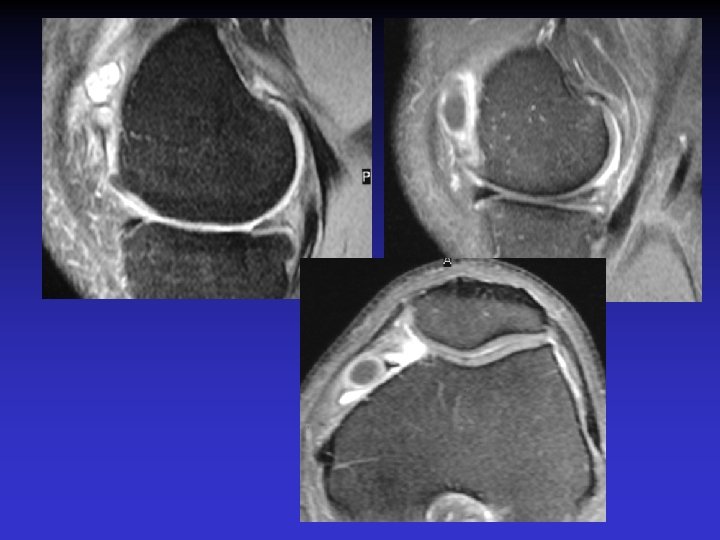

ASPECT IRM • • Hyposignal TI Hypersignal T 2 Pas de prise du contraste après Gado IV Continuité conservée du LCA+++ avec dilacération des fibres • Aspect en « tige de céleri »

GADO

GEODES SYNOVIALES • En regard des zones d’insertion fémorale et / ou tibiale • Hypo TI Hyper T 2 • Rehaussement possible après Gado IV

ASSOCIATION A DES KYSTES MUCOIDES • Dans près de 50% des cas • Au contact ou à distance du LCA